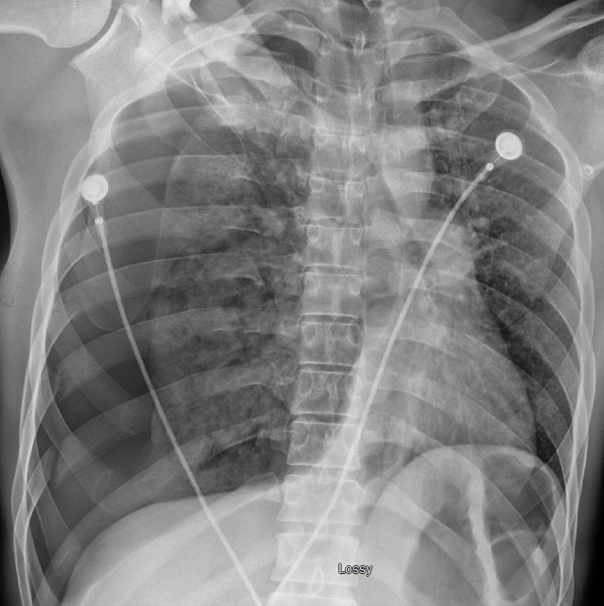

Imaging of the chest is a key part of evaluating patients who sustain blunt thoracic trauma. Chest X-ray is typically the first-line study because it is widely available and quick to perform. However, chest x-rays are not very sensitive and can miss subtle injuries.

Guidelines have been developed to help determine which patients truly need further imaging with chest CT, to both avoid missing injuries but also to avoid excessive use of CTs that can lead to increases in radiation exposure and healthcare costs.

Chest X-ray: Can diagnose SOME pneumothoraces. An upright chest radiograph is more specific than supine imaging for the detection of pneumothorax; however, in the trauma setting, patients are frequently imaged in the supine position, which significantly reduces diagnostic sensitivity.

eFAST: Bedside ultrasound has therefore demonstrated better sensitivity in trauma patients for identifying pneumothorax.

Hemothorax results from accumulation of blood in the pleural space, most often due to rib fractures lacerating intra-thoracic vasculature or injury to lung parenchyma. Clinical signs include respiratory insufficiency, decreased breath sounds, and in severe cases, hypotension. These are usually identified on x-ray imaging or CT but can also be seen on eFAST exam.